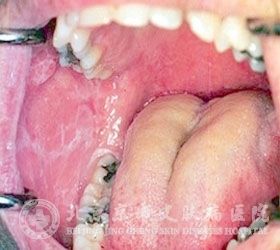

口腔扁平苔藓的症状是什么?口腔扁平苔藓是一种常见的疾病。很多人口腔扁平苔藓的关注就是必要的。了解口腔扁平苔藓的相关注意事项,可以让口腔扁平苔藓皮肤病患者朋友 的配合医生的治疗,以达到 的口腔扁平苔藓皮肤病治疗结果。为此,北京京城皮肤医院将会详细介绍口腔扁平苔藓症状有什么,希望可以帮助患者朋友早日摆脱口腔扁平苔藓。

北京京城皮肤病专家指出,早期的口腔扁平苔藓一般无自觉的症状,一般没有疼痛感或者仅有轻微刺痛,因为口腔炎症的影响,使得黏膜变得粗糙,口腔原有的其绵软性、弹性也遭到损害。随着病情的发展,一般会出现黏膜会浮现充血、水泡甚至糜烂。不易治疗,很高。

1、扁平苔藓图片